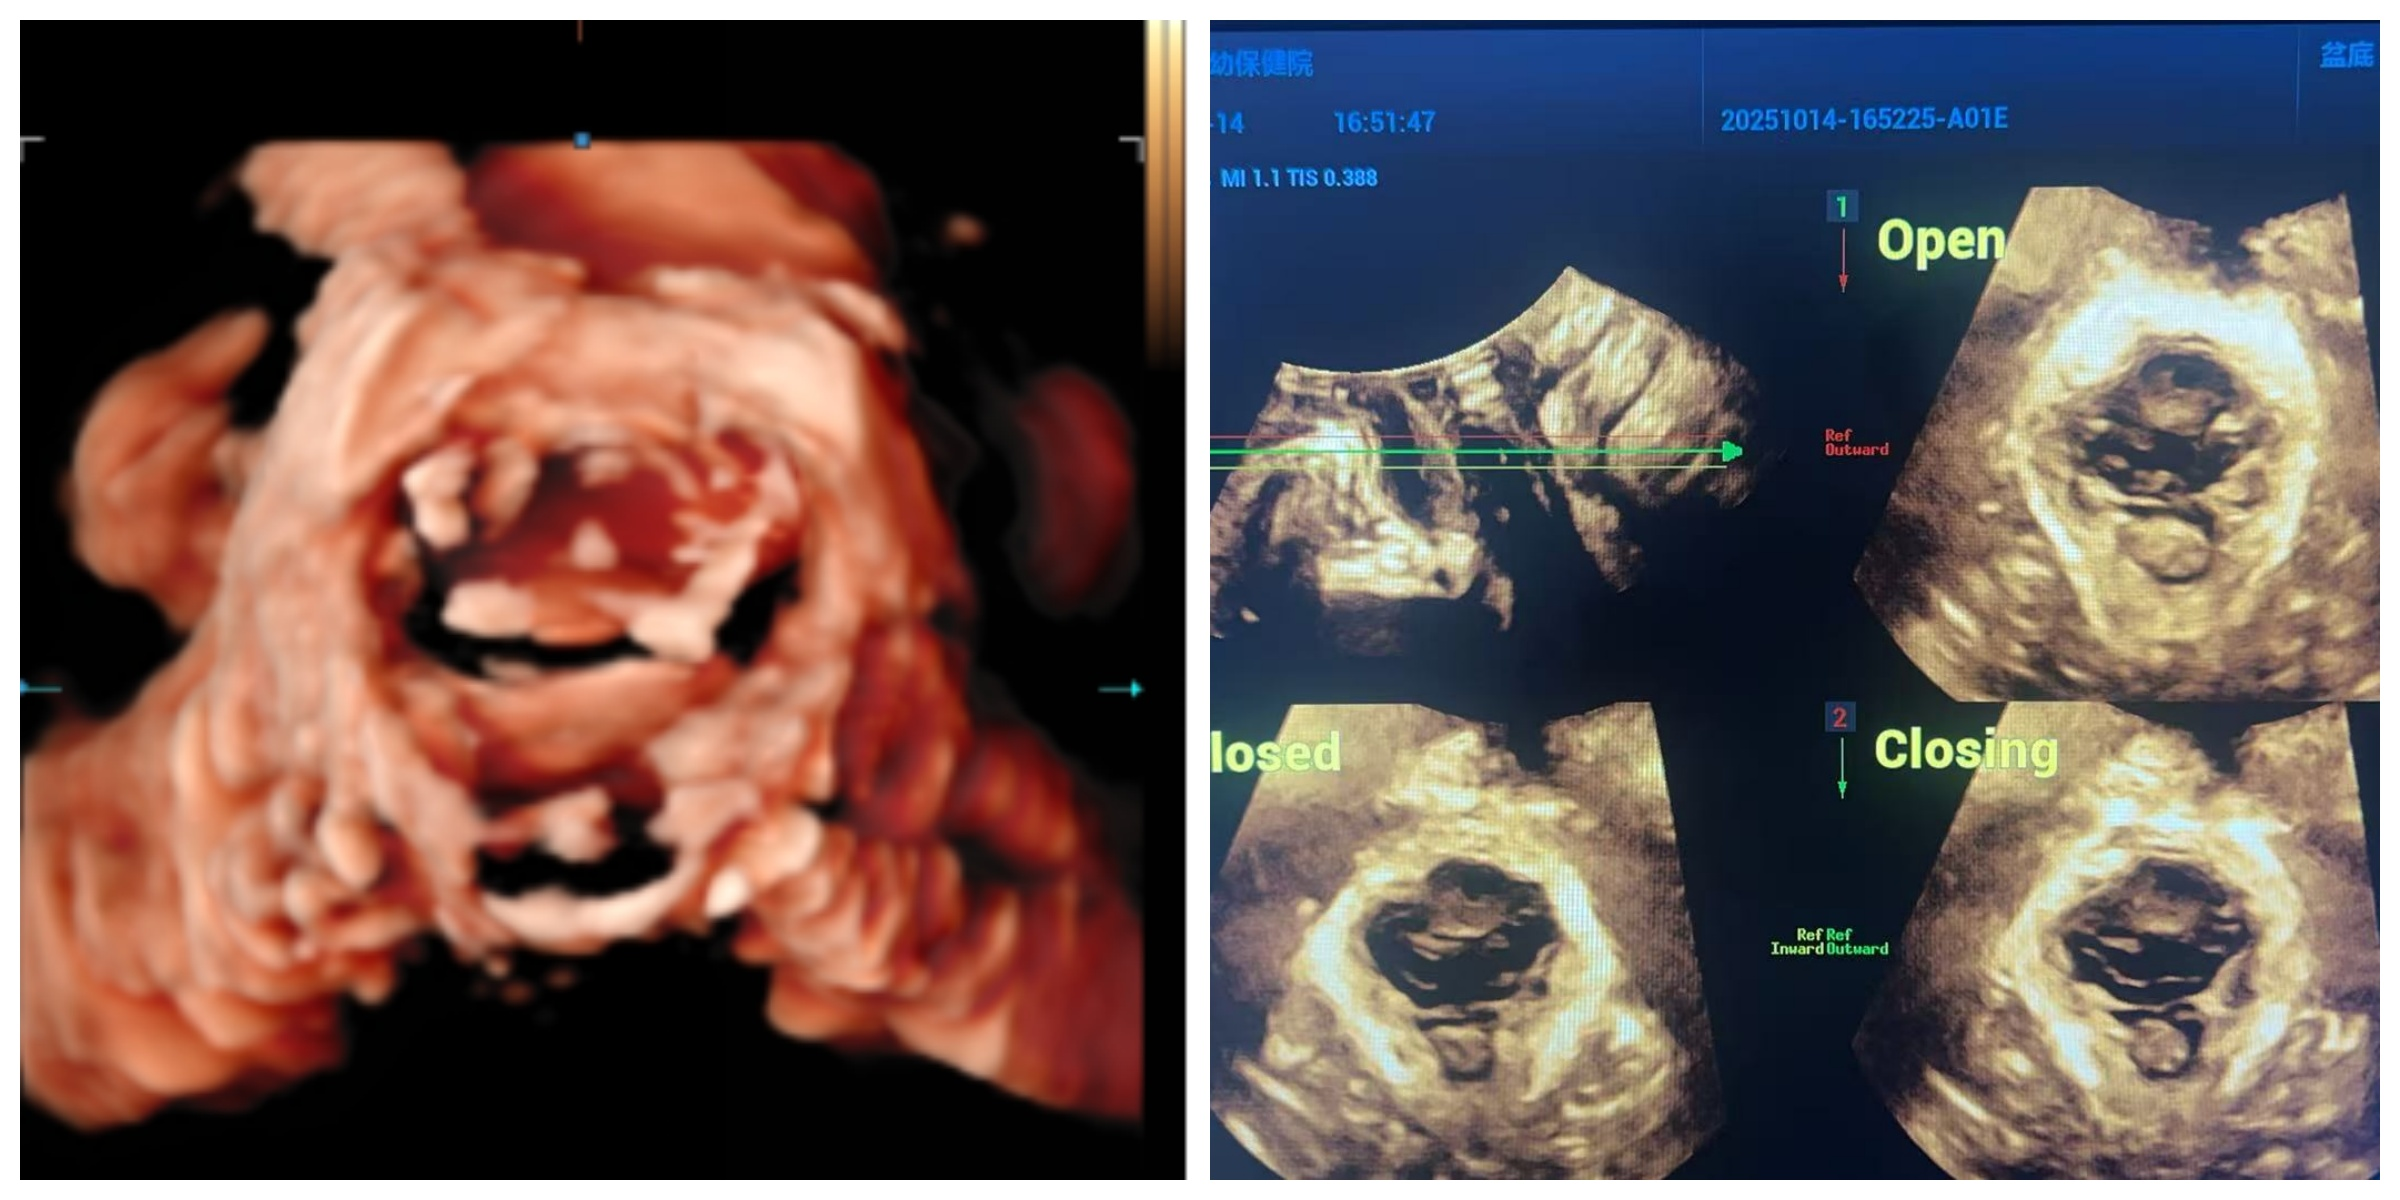

提到医学检查,很多人会担心疼痛或侵入性操作,但盆底超声完全无需顾虑。它具备安全无创、操作便捷的核心优势,检查过程简单又舒适:你只需安静躺在检查床上,医生会将特制的超声探头轻柔置于会阴部,无需侵入体内。随后,通过动态影像,医生能清晰捕捉到你在不同状态下的盆底变化,比如:

咳嗽、用力屏气时,膀胱颈是否出现过度下移;

主动收缩盆底肌群时,肌肉能否协调、有力地 “托举” 器官;

是否存在子宫、膀胱等器官膨出的早期迹象,肛提肌裂孔是否松弛变形。

更重要的是,盆底超声能实现精准量化评估—— 不是模糊的 “感觉有问题”,而是明确给出数据:比如膀胱颈移动度是否超过正常范围,肛提肌裂孔面积是否异常增大,静息状态下盆膈是否出现不该有的低平。这些清晰的影像和数据,让隐匿的盆底问题无所遁形。